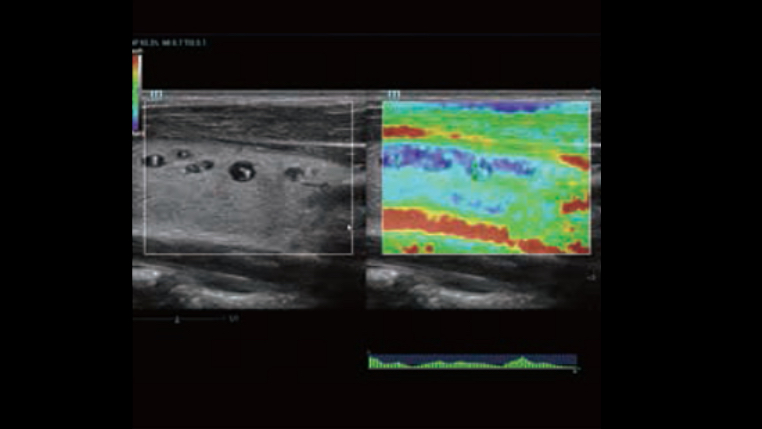

Dynamic Pixel Focusing technology allows the Resona 6 to achieve extreme uniformity in pixel level throughout the whole field of view. Now there's no need to adjust the focal positions to achieve uniformity across patient exams.

HD Scope: By processing channel data retrospectively, HD Scope enables tissue-specific enhancement with improved detailed information and image contrast on specific region of interest.